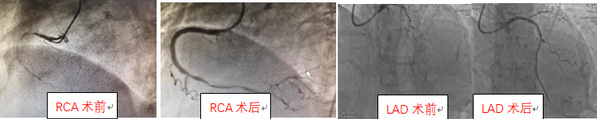

造影顯示患者的心臟中樞道路——原先重度狹窄扭曲鈣化的前降支次全閉塞了。手術(shù)參加人員楊煜主任、陸遠(yuǎn)主任、張敏、段洋主治醫(yī)師按照術(shù)前制定的手術(shù)策略:首先IABP支持下,導(dǎo)絲順利通過、球囊小壓力擴(kuò)張后恢復(fù)前降支的血流、遠(yuǎn)端引流良好;第二步高速旋轉(zhuǎn)(15萬轉(zhuǎn)/分)旋磨頭,5次短促旋磨一點(diǎn)點(diǎn)通過鈣化病變,老人心率血壓均穩(wěn)定,臺(tái)上醫(yī)生們懸著的心終于放下了;第三步高壓球囊擴(kuò)張后,IVUS(血管內(nèi)超聲)指引下支架順利植入,手術(shù)成功(圖四)。

圖四:術(shù)前術(shù)后冠狀動(dòng)脈血管對(duì)比